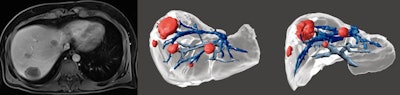

Left images: 3D model for interventional planning in a 5-year-old boy with a congenital intrahepatic portosystemic shunt. Right images: 3D model after shunt closure with Amplatzer device (silver color) in a 4-year-old boy with a congenital portosystemic shunt.

Left images: 3D model for interventional planning in a 5-year-old boy with a congenital intrahepatic portosystemic shunt. Right images: 3D model after shunt closure with Amplatzer device (silver color) in a 4-year-old boy with a congenital portosystemic shunt.The development and availability of new virtual reality (VR) technologies in the near future may limit the need for printed models, the authors cautioned.